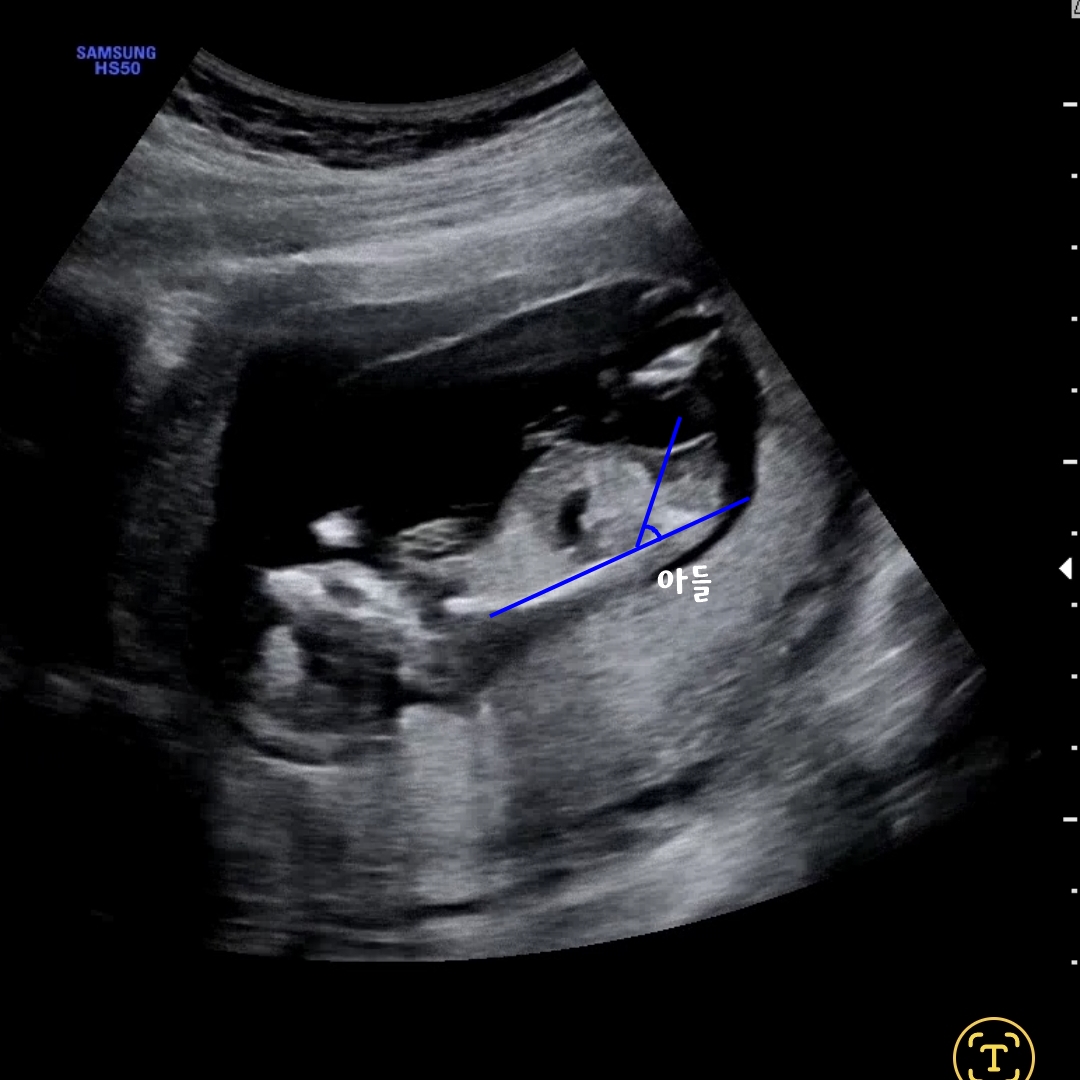

각도법

임신 11~14주 사이의 초음파에서 사용되는 성별예측법이에요.

이 시기엔 남아여아 모두 성기가 돌출되어있는데 성기의 각도를 보고 성별을 예측합니다.

척추와 성기 사이의 각도가 30도 이상 : 아들

척추와 성기사이의 각도가 30도 이하 : 딸

장꾸맘 후기

장꾸맘이라고 유명하신 각도법의 대가님이 계십니다.

12주에 니프티검사를 하고나서 2주의 기다림이 있었는데

이때 확인한 초음파동영상으로 각도법 문의를 했었습니다.

2일정도 걸렸지만 딸이라는 답변 받았습니다.

저는 아무리 봐도 모르겠던데;;; 정말 대단하신 것 같아요.

각도법도 성별일치했어요!!!!!